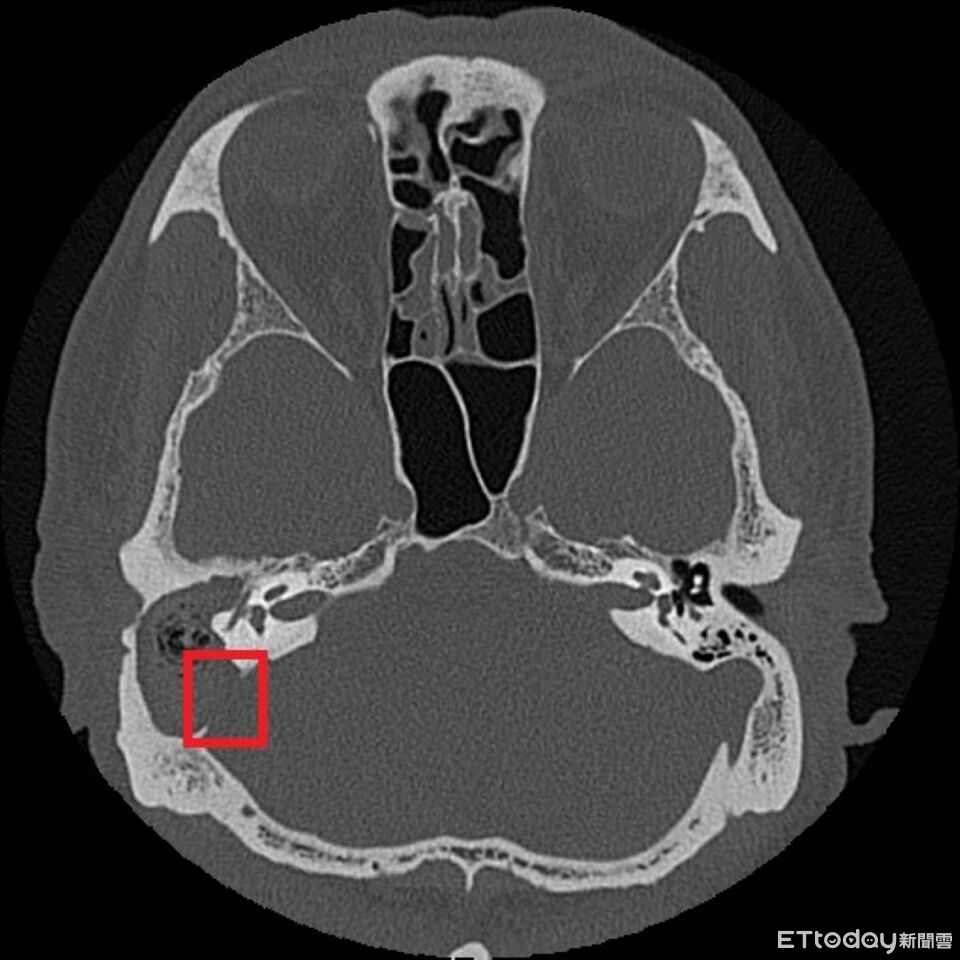

▲從張先生的影像可看到與後顱窩相隔的骨板遭膽脂瘤侵蝕(紅框處)。(圖/台北慈院提供)

鄭靜雯表示,經顳骨電腦斷層檢查後,確認為慢性中耳炎併發膽脂瘤,且已侵蝕顱底骨質,需立即住院,並以抗生素控制感染,待發炎情形穩定再安排手術,先打開乳突骨,完整清除病變組織,並同步進行鼓室重建、外耳道成形及顱底缺損修補,術後恢復良好。